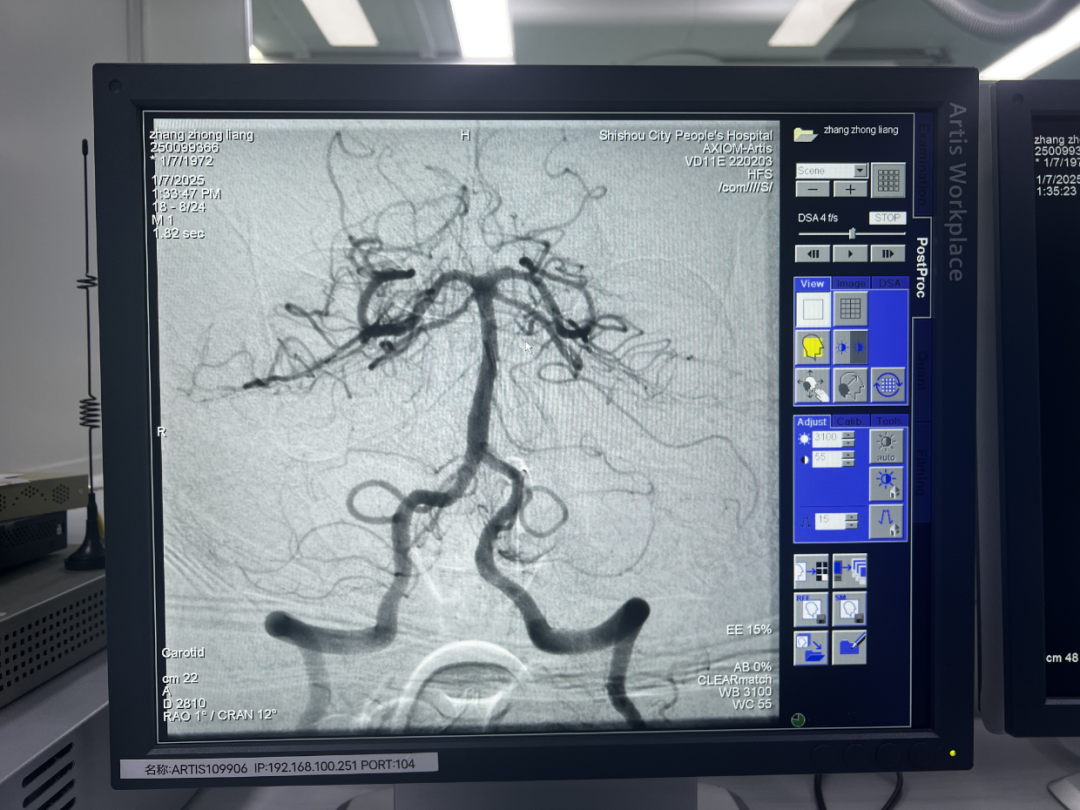

2025年1月6日17时34分,53岁的患者张某某因头晕伴右侧肢体无力7.5小时由调关镇卫生院紧急送往石首市人民医院救治。患者称上午10时左右在活动中突感头晕、右侧肢体无力且持续未缓解。 张某某入院时,生命体征虽平稳,但神经系统已有明显症状。神经内科医师朱立平经过细心诊察,初步诊断为“脑梗塞”,并制定详细的治疗方案。次日上午9:20分,患者病情突变。护士王萍巡视发现患者神志为嗜睡状、表情淡漠、左侧肢体全瘫,头颈部CTA检查后,考虑为血栓脱落。神经内科团队迅速组织讨论与会诊,介入室随即投入战斗。 由神经内科主任张伟、医师朱立平、介入专科护士汪杨组成的团队紧密协作,通过脑血管造影,明确了患者“右侧大脑后动脉闭塞”这一关键病因。时间就是生命。面对发病23小时后仍在不断衍变的进展性脑卒中,神经内科团队在荆州市中心医院神经内科专家陈立教授的指导下,成功抽吸,取出血栓,术后造影显示:“基底动脉及双侧大脑后动脉恢复通畅”。 手术结束后,张某某安返病房。在医护人员的精心治疗护理下,张某某神志转清,病情稳定,双侧肢体肌力恢复,精神状态显著改善。 此次颅内动脉取栓术的成功,彰显了市人民医院神经内科的精湛技术和团队精神。神经内科将秉持初心,砥砺前行,不断钻研新技术,开展新业务,为全市脑血管疾病患者保驾护航。